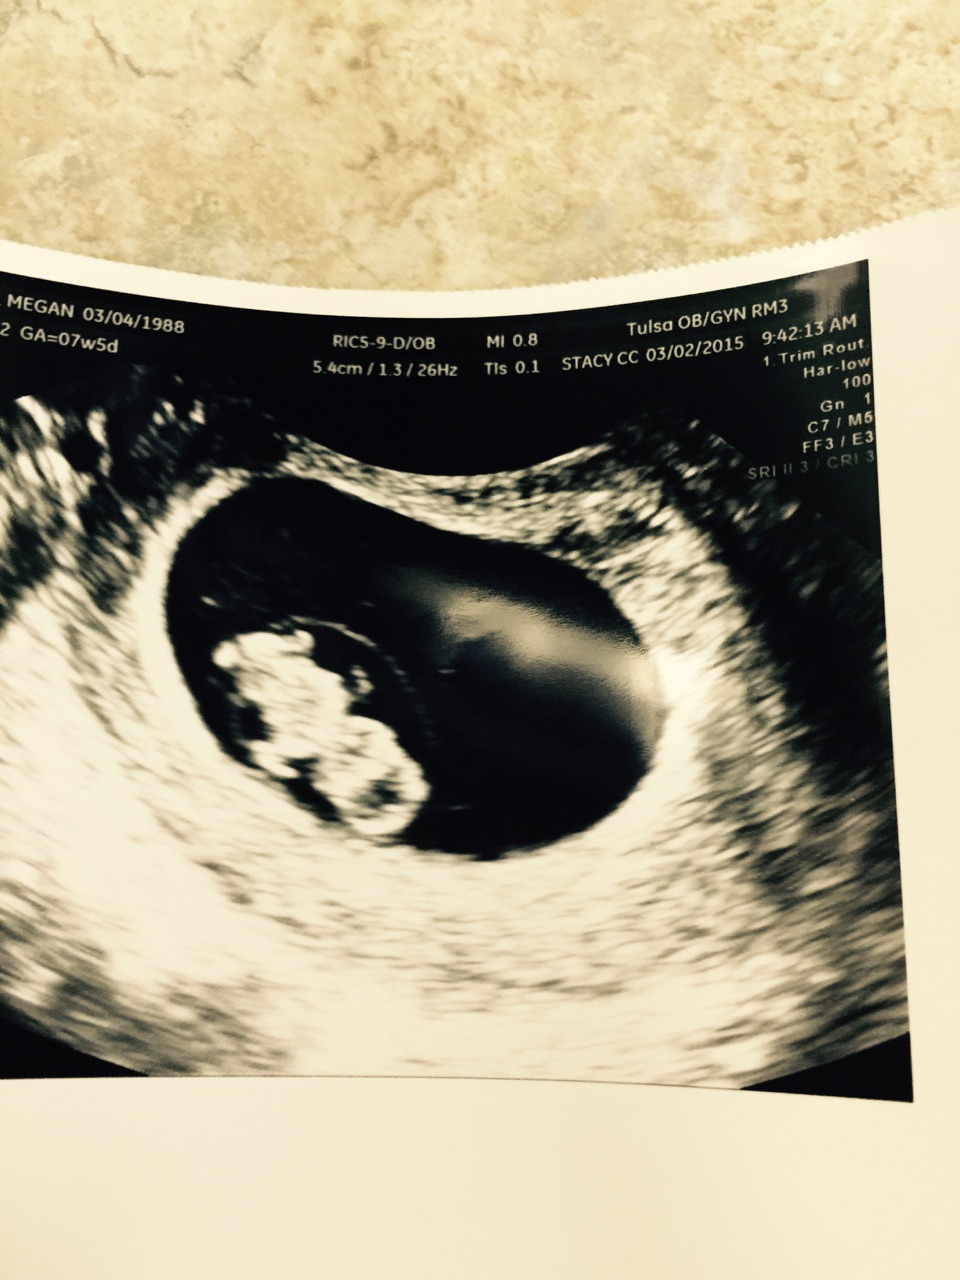

• Lil dinosaur 7w5d heartbeat 175! :x